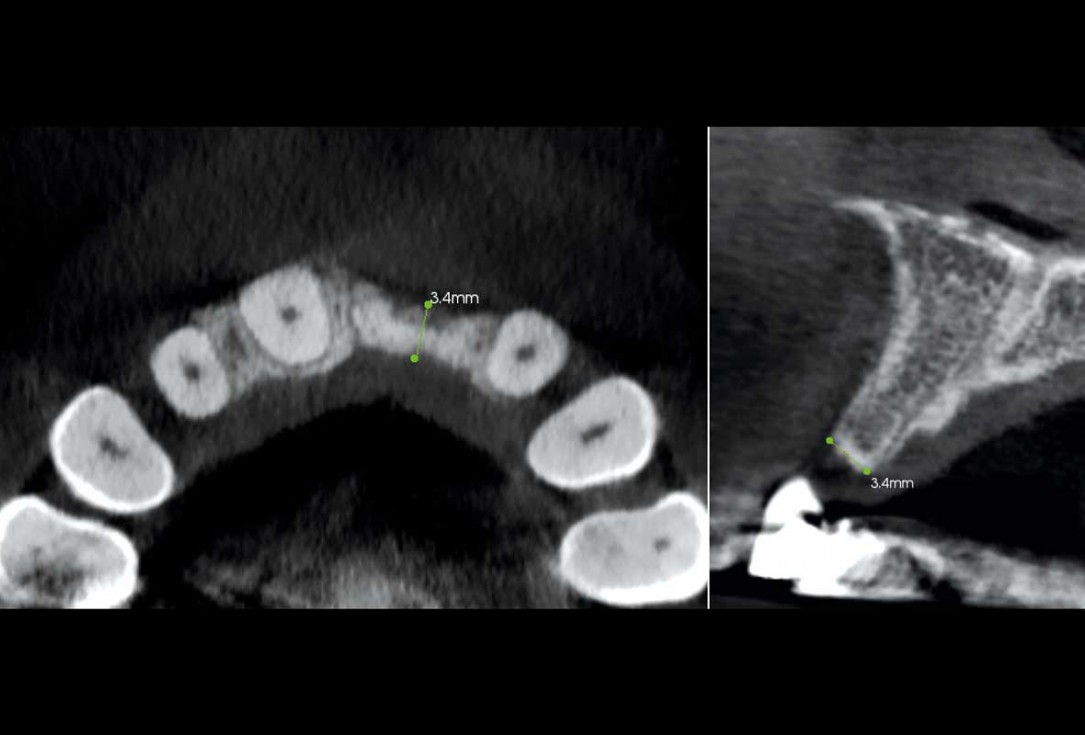

3/35 - CBCT: Advanced bone loss after traumatic tooth loss more than 10 years agoBlock grafting in the aesthetic zone with maxgraft®, Jason® membrane and cerabone® - Dres. H. Maghaireh and V. Ivancheva